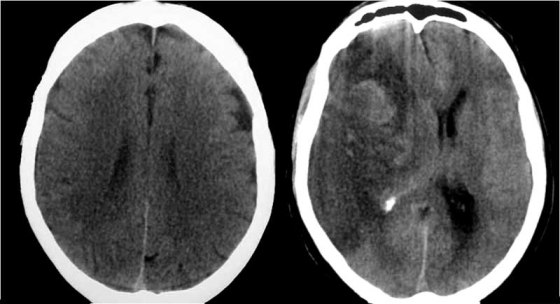

SIGNO DE LA PÉRDIDA DE SURCOS

Sutil pérdida de surcos en la convexidad derecha. En la TC de control se observa un infarto masivo en el territorio de la ACM derecha, con zonas hiperdensas por transformación hemorrágica.

La disminución del número y profundidad de los surcos de la convexidad cerebral es un signo poco específico, que se ha descrito como hallazgo precoz en el infarto isquémico cerebral. Está relacionado con el edema citotóxico que acompaña a la isquemia. También puede aparecer en el edema cerebral difuso y acompañando a lesiones expansivas cerebrales.